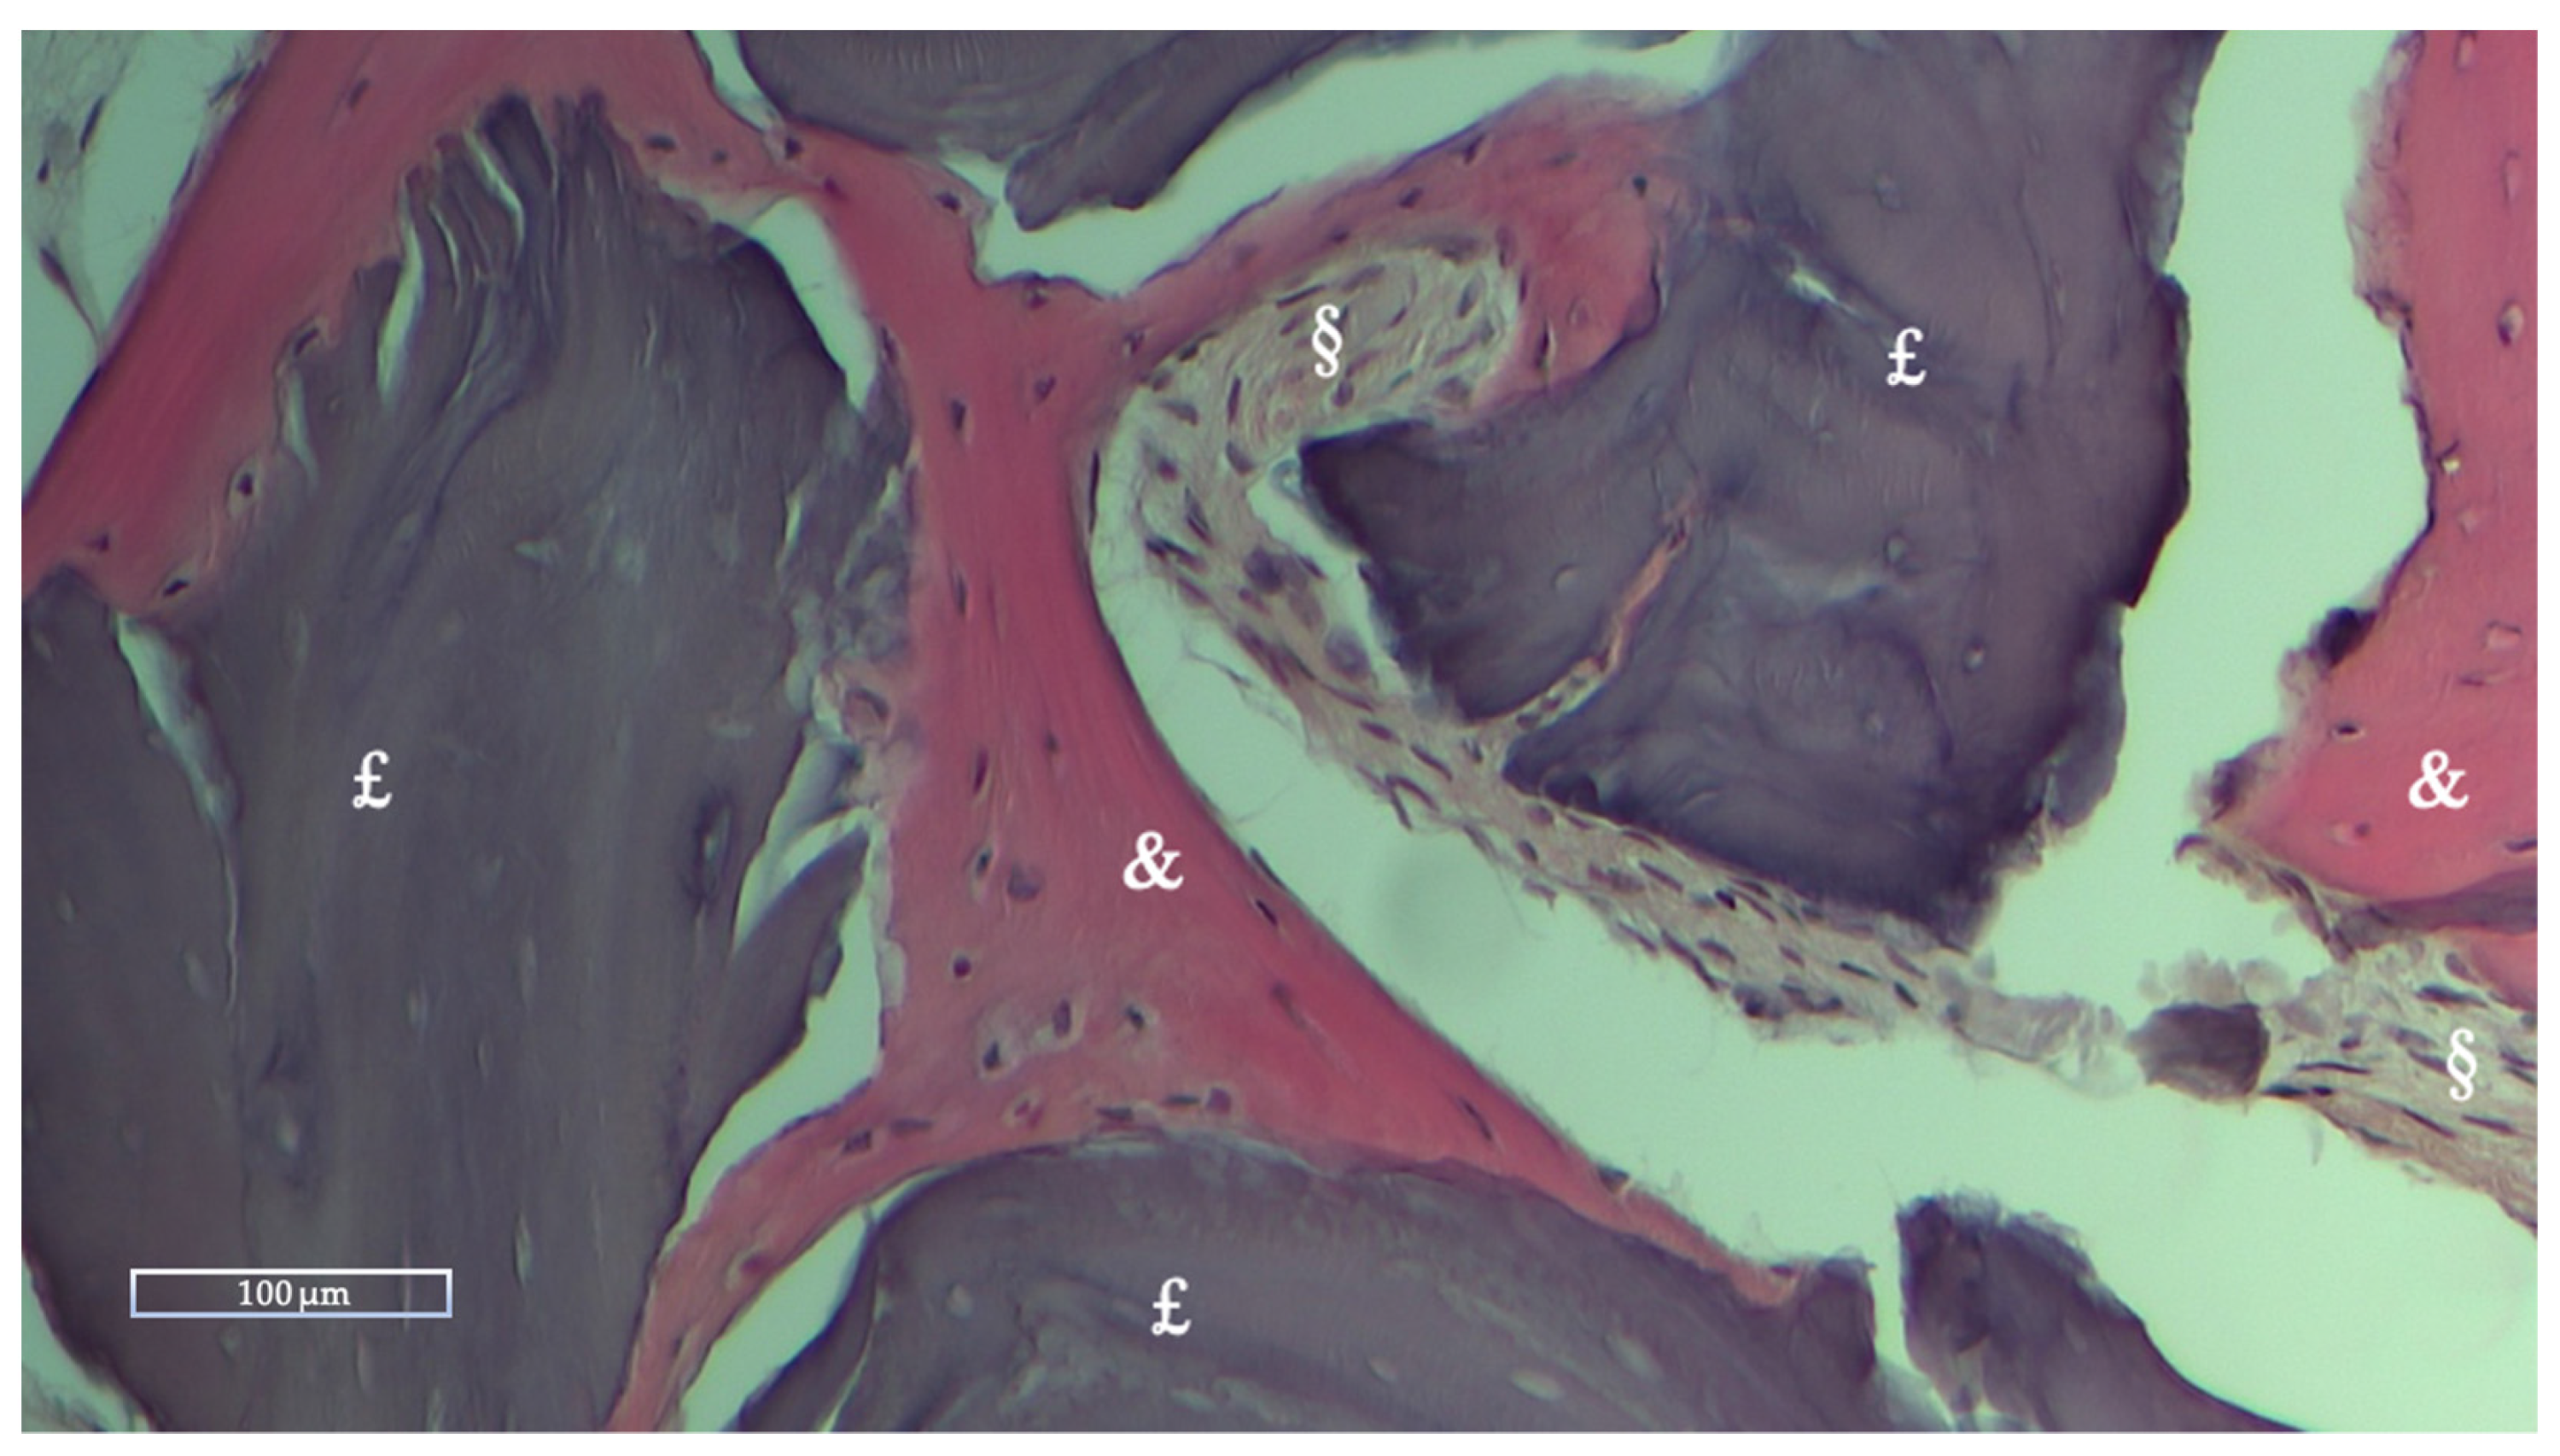

Histologic and Histomorphometric Results

| NFB | RB | SF | |

|---|---|---|---|

| Mean % ± Std dev | 28.27 ± 10.62 | 10.39 ± 12.01 | 61.33 ± 12.08 |

| Range % (Min-Max) | 16.51–59.74 | 0–36.89 | 40.26–75.59 |